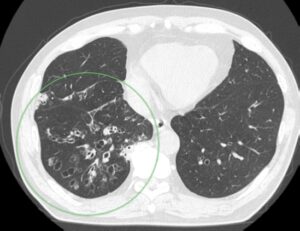

(症例2)

胸部CT(輪切り像)で気管支の嚢胞状拡張(指輪のような形)を認める(緑の〇印)